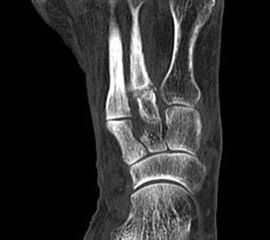

Entsprechend den beiden vorrangigen Manifestationsorten kann zwischen der Insertionstendopathie der Achillessehne am knöchernen Ansatzpunkt des Fersenbeines und der weiter proximal im freien Sehnenverlauf gelegenen, und daher „non-insertionalen“ oder „mid-portion“ Tendopathie unterschieden werden.

Die mid-portion Tendinopathie befindet sich in der Regel distal der myotendinösen und proximal der tendoossären Übergangszone.

Hier befindet sich ca. 3-5 cm proximal des Tuber calcanei ein als „kritische Zone“ benannter Bezirk, der durch eine ungünstige arterielle Blutzufuhr gekennzeichnet ist (letzte Wiese). Hier finden sich häufig spindelförmige Schwellungen, die bei MRT-Diagnostik nicht selten partielle Nekrosen und Partialrupturen der Achillessehne aufweisen (Abb. 14).

Unabhängig davon können insbesondere chronische Insertionstendinosen der Achillessehne von Partialrupturen (Abb. 15) und erosiven Läsionen des dorsalen Fersenbeines begleitet sein.